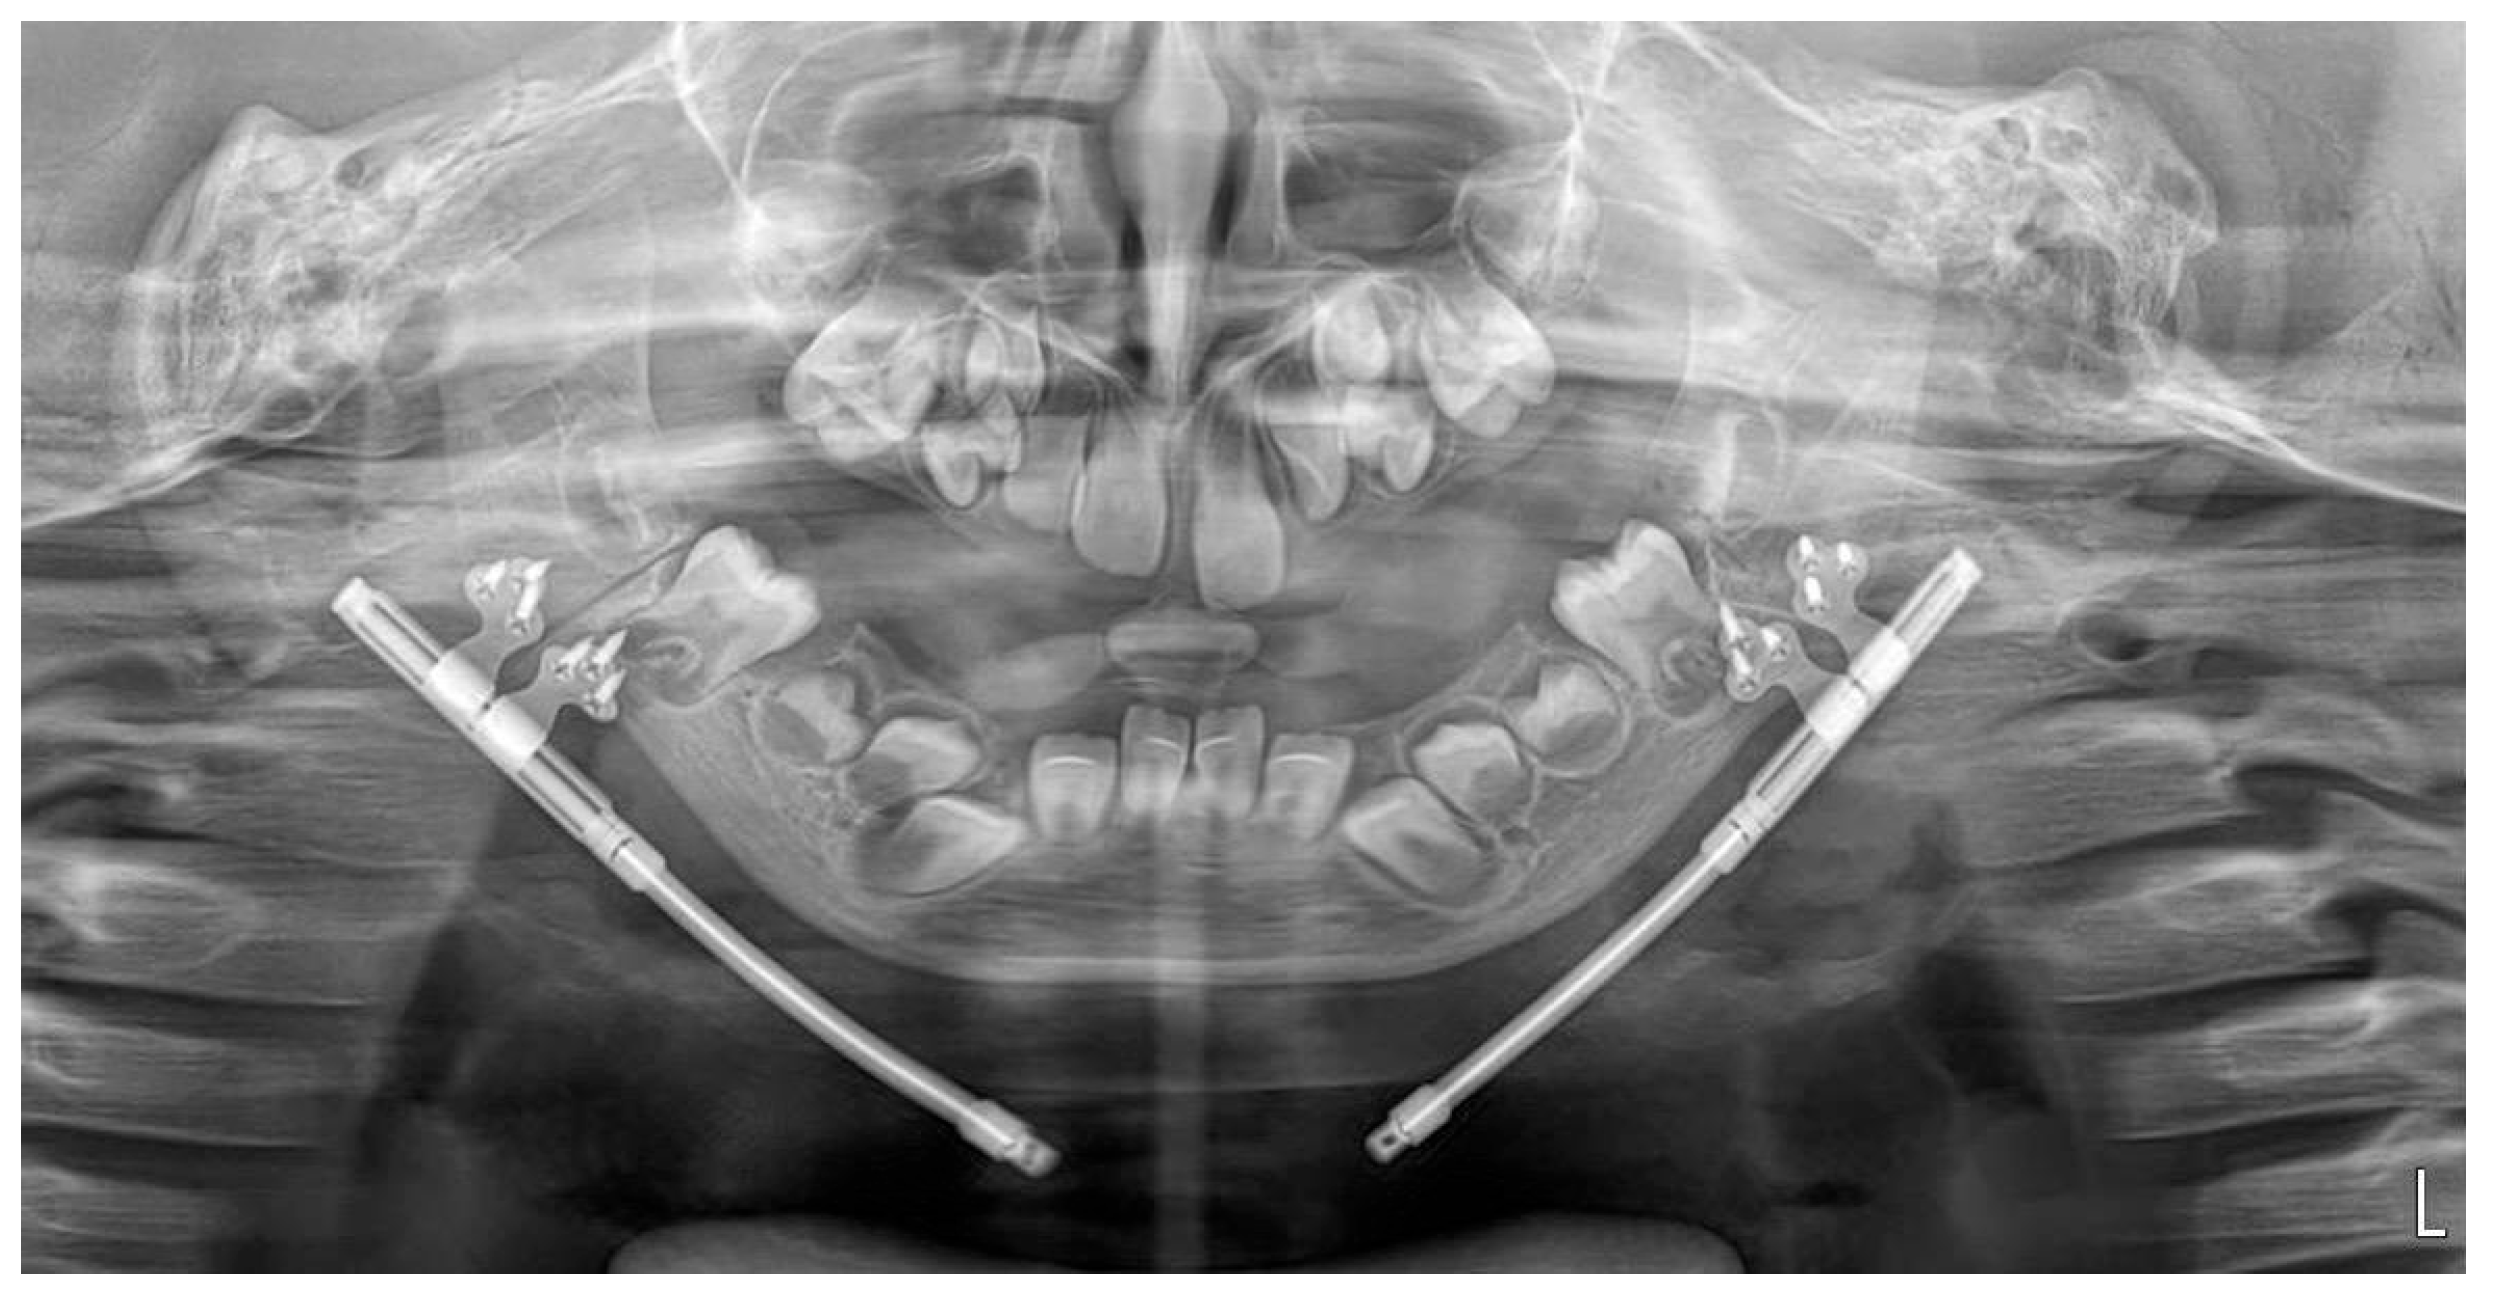

During the distraction and consolidation phases, we recorded the condition of the callus and its subsequent ossification by combining panoramic images and ultrasound examinations. Ultrasound examinations were performed with a 13 MHz linear transducer, without sedation. The ultrasound beam was oriented perpendicularly to the bone surface. The distractors were identified by characteristic metal echoes, and the osteotomy gap was visualized clearly, given the contrast between the gap and normal bone. Initial ultrasound findings indicated early callus formation with visible ossification. The ossification gap was measured at both cranial and caudal margins, and Doppler imaging confirmed vascularity within the callus, with no signs of infection. Further ultrasound evaluations were conducted at 6 and 16 weeks post-distraction, assessing the same parameters. Callus ossification progressed without signs of infection. At week 16, ultrasonography demonstrated a continuous, echogenic cortical line at both the cranial and caudal margins of the distraction zone, absence of a residual hypoechoic gap, and preserved intraregional Doppler signal, indicating a well-vascularized, mature callus. Panoramic radiography at the same time point confirmed cortical bridging across the distraction gap (Figure 7 and Figure 8). On the basis of these combined findings, the distraction was considered stable, and the distractors were scheduled for removal.

Figure 7. Panoramic radiograph obtained at 16 weeks after completion of distraction, immediately before removal of the distractors.

N/A: not available; ICU: intensive care unit. Representative panoramic radiographs and ultrasonographic images for days 6, 21, 42 (week 6), and week 16 post-distraction are shown in Figure 5, Figure 7 and Figure 8.